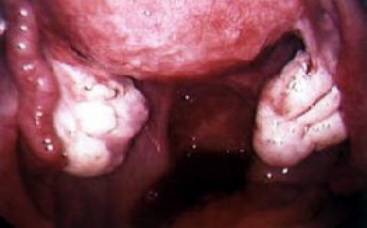

Aspecte patologice ale regiunii tubo-ovariene

Chist ovarian torsionat Chist ovarian endometrial rupt

Cancer de

ovar

Sarcina ectopica tubara

Hidrosalpinx